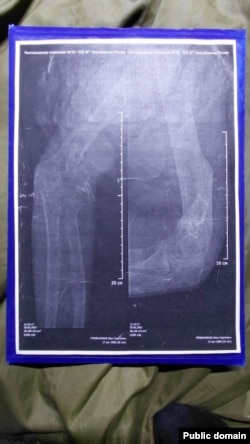

"Не производят ВВК (военно-врачебная комиссия), никакой медкомиссии, в теле пуля, рука переломана. Домой не отпускают", – говорит Гребенников на камеру, когда его в составе 35-й отдельной гвардейской мотострелковой бригаде (в/ч 41659) везут вместе с другими пленными после обмена в Донецк. До этого Гребенников записывал видео, как его за отказ возвращаться на фронт посадили в камеру в его воинской части.

Согласно меддокументам Гребенникова, 30 июня 2025 года врач-невролог провел осмотр и поставил диагноз, указав категорию годности к военной службе – "Д" (полностью не годен). Невролог дал направление Гребенникову в Брянку (город в Луганской области Украины) для "лечения, прохождения военно-врачебной комиссии (ВВК) и официального определения категории годности". Однако все назначения врача командование проигнорировало – Гребенникова и других раненых, возвращенных после плена, насильно отправили на фронт.

– Нам казалось, что после возвращения из плена нас хотя бы лечить будут. Куда там – нам в наглую поменяли категории на фальшивые – мне, например, мою "Д" заменили на "Б" (годен к службе с незначительными ограничениями), хотя у меня правая рука как была в нескольких местах перебита – так и висит. У меня до сих пор пуля в теле – даже не оперировали, – говорит Иван. – И нас таких очень много – на костылях, в гипсе. Им просто по**й, везут на Донецкое направление калек.